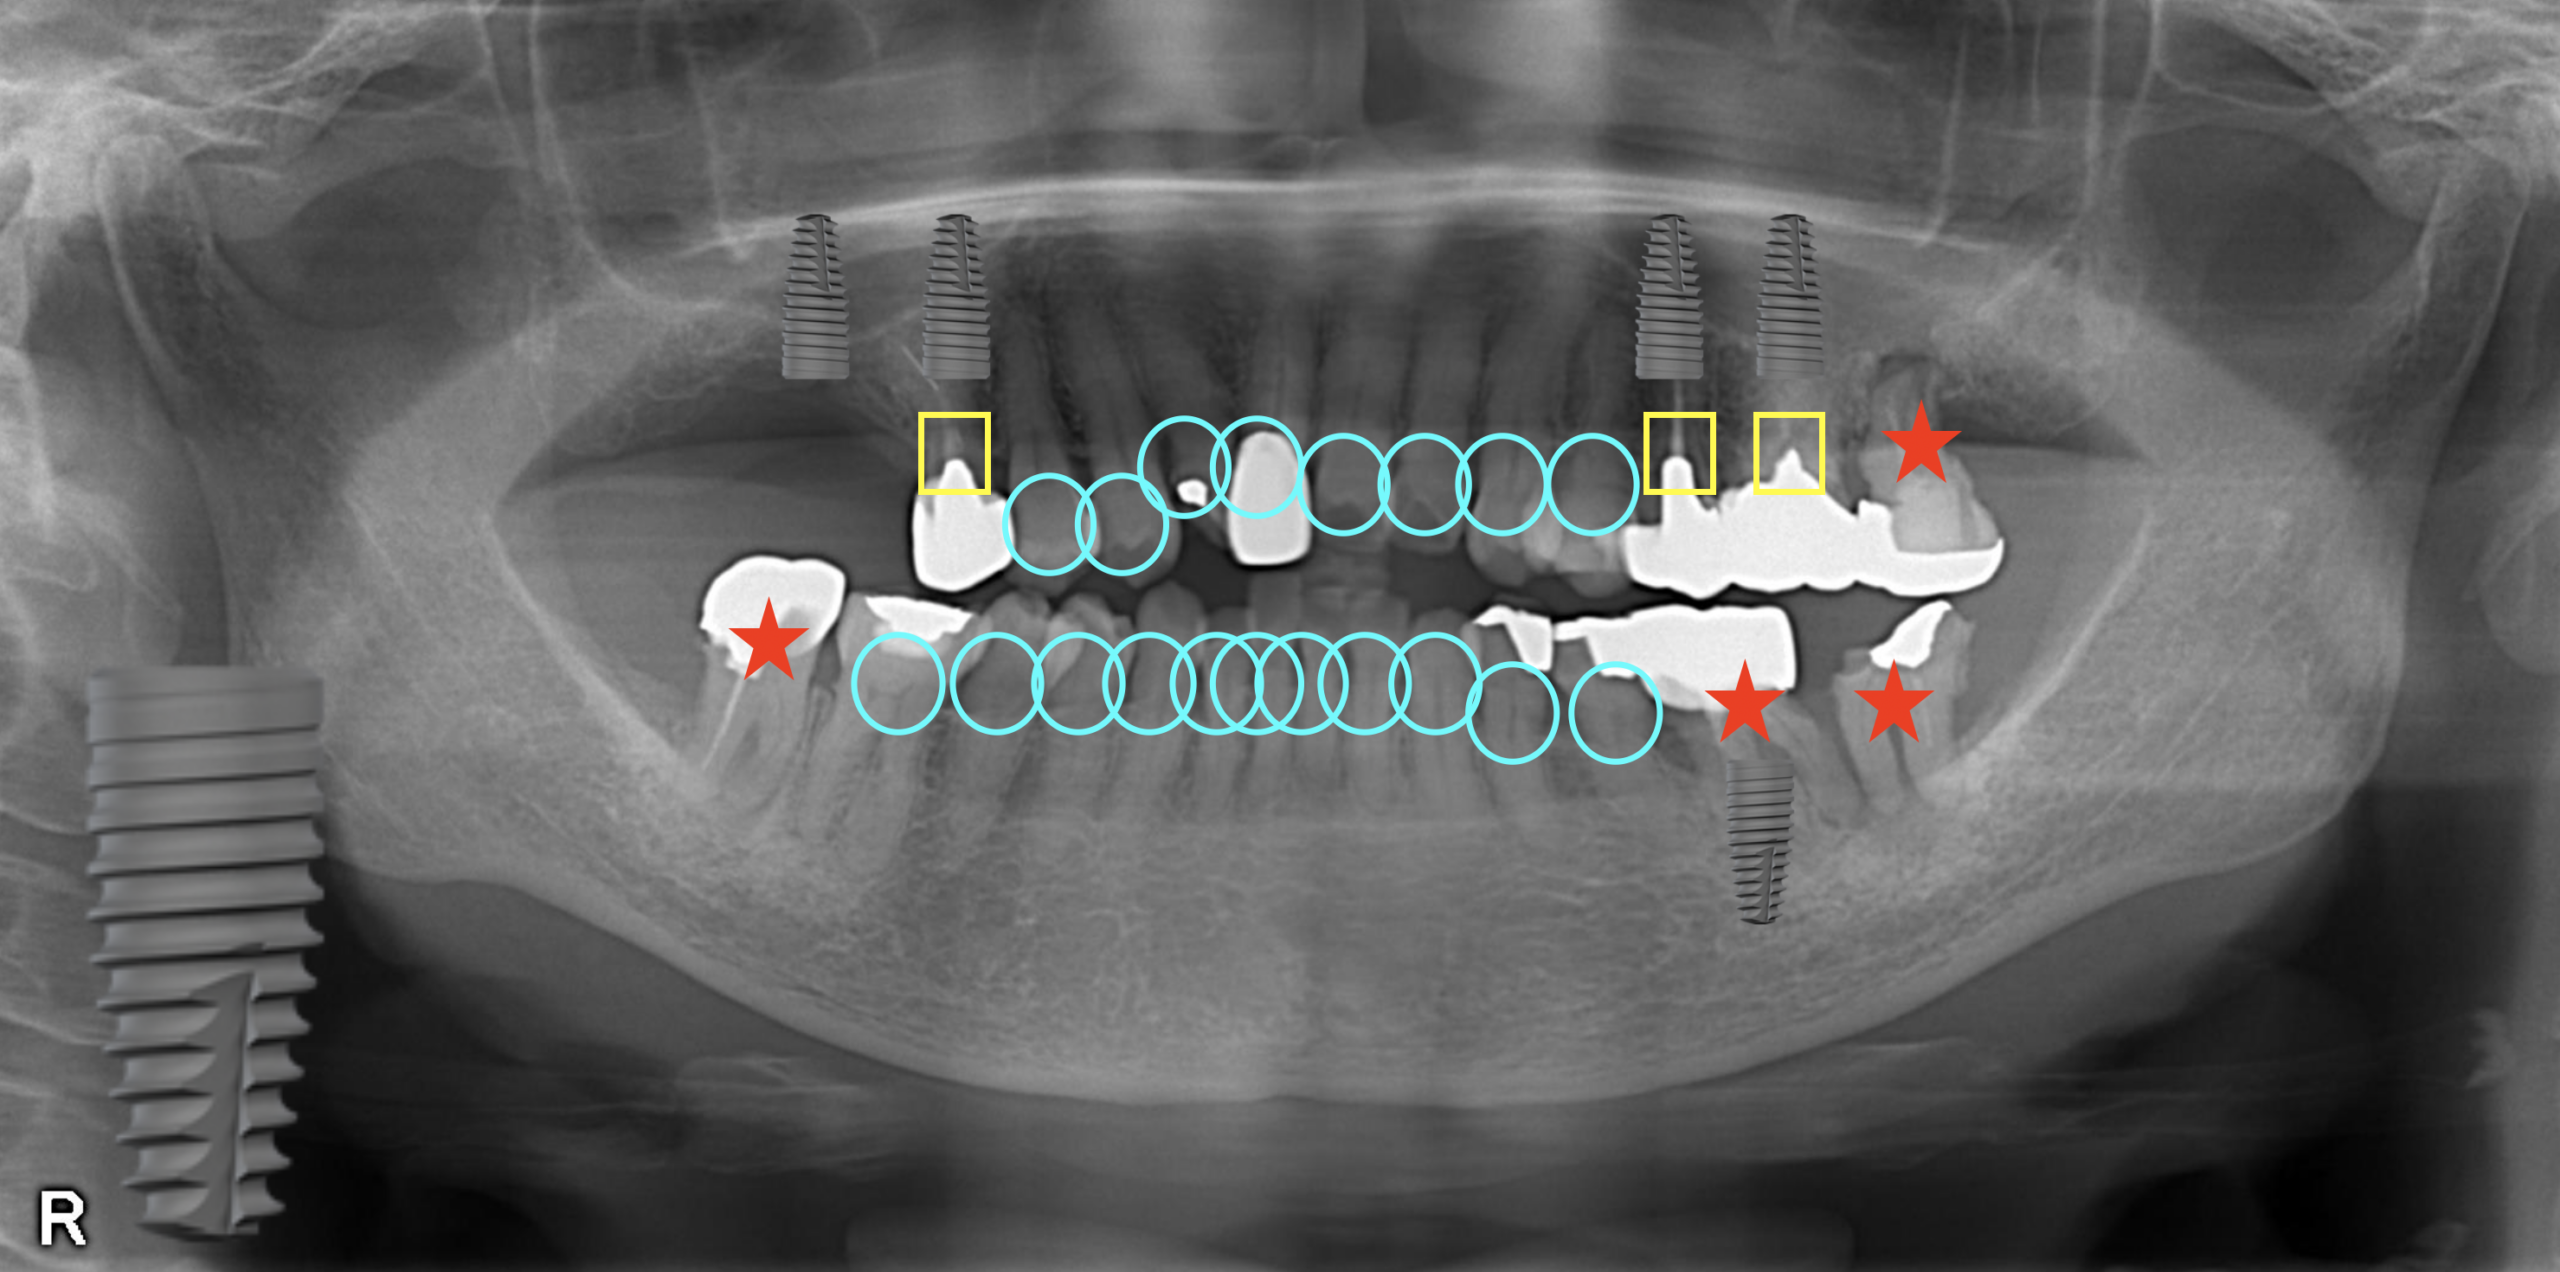

パノラマレントゲン写真です。

右と左が逆に撮影されるので、画像の右が、患者さんの言う左、画像の左が、患者さんの言う右、になります。

:青の丸をつけた歯はおそらく最後まで残ると予想される歯

:黄の四角をつけた歯はいつか何かしらのトラブルが起こるだろうと予想される歯

:赤の星をつけた歯は現時点でいつ症状が出てもおかしくない、もしくは寿命が短いと予想される歯

レントゲンから前歯が噛んでいない、開咬状態だということがわかります。アンテリアオープンバイトと言われる状態です。

向かって左上のインプラント治療は、第1大臼歯までを補うという意味合いから必要だと考えます。

左上のインプラントの歯は、左下の奥から2番目の青い丸の歯と噛むことになります。

左下の赤い星の歯は、第2大臼歯であること、また噛む歯がないため、抜歯することになります。

一番右下の赤い星の歯(第2大臼歯)は、骨がないことから抜歯することになります。

右下の右から2番目の赤い星の歯(第1大臼歯)は、今治療して仮に治ったとしても10年後、20年後にちゃんと歯として成立している確率は低いこと、また10年後には70代になっていて、70代になってから再治療になるのはおそらく難しい、という判断から抜歯することになります。

第1大臼歯は咀嚼にも重要な歯なので補うことを考えないといけません、この部位にはインプラント治療が必要でしょう。

右上の赤い星の歯(第2大臼歯)は、骨がないこと、根尖病変が小さくはないこと、虫歯があること、噛み合わせが不利なこと、噛む歯がないことから、抜歯判断になります。

つまり、治療開始時点で4本の抜歯、2本のインプラント治療が必要です。